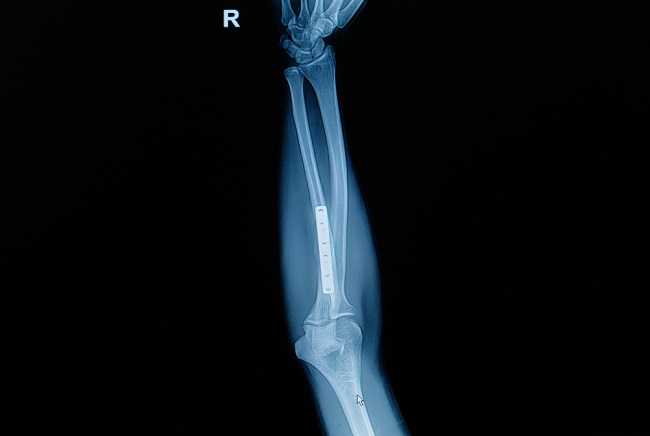

Teknik untuk reduksi terbuka sangat beragam, dan harus disesuaikan dengan setiap jenis fraktur pada setiap jenis tulang. Terdapat banyak jenis alat yang dapat digunakan untuk fiksasi internal setelah reduksi terbuka fraktur, seperti plate, screw, wire, dan alat-alat tersebut memiliki beragam bentuk dan fungsi kombinasi.[2,4,5]